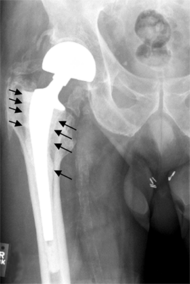

Intraoperative fractures may occur. After surgery, bones with internal fixation devices in situ are at risk of periprosthetic fractures at the end of the implant, an area of relative mechanical stress. Post-operative femoral fractures are graded by the Vancouver classification.

On radiography, it is normal to see thin radiolucent areas of less than 2 mm around hip prosthesis components, or between a cement mantle and bone. These may indicate loosening of the prosthesis if they are new or changing, while areas greater than 2 mm may be harmless if they are stable.[29] The most important prognostic factors of cemented cups are absence of radiolucent lines in DeLee and Charnley zone I, as well as adequate cement mantle thickness.[30] In the first year after insertion of uncemented femoral stems, it is normal to have mild subsidence (less than 10 mm).[29] The direct anterior approach has been shown to itself be a risk factor for early femoral component loosening.[31][32][33]